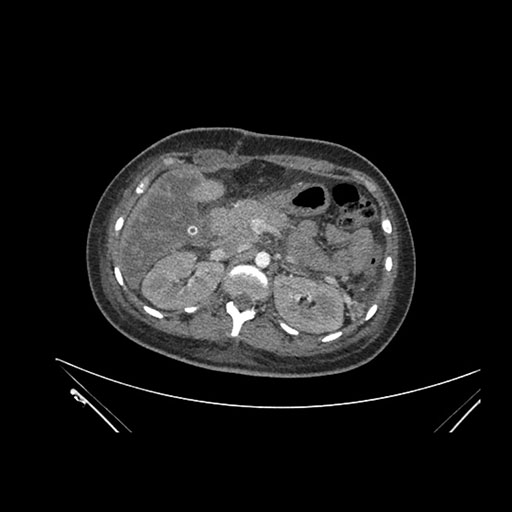

Axial Arterial